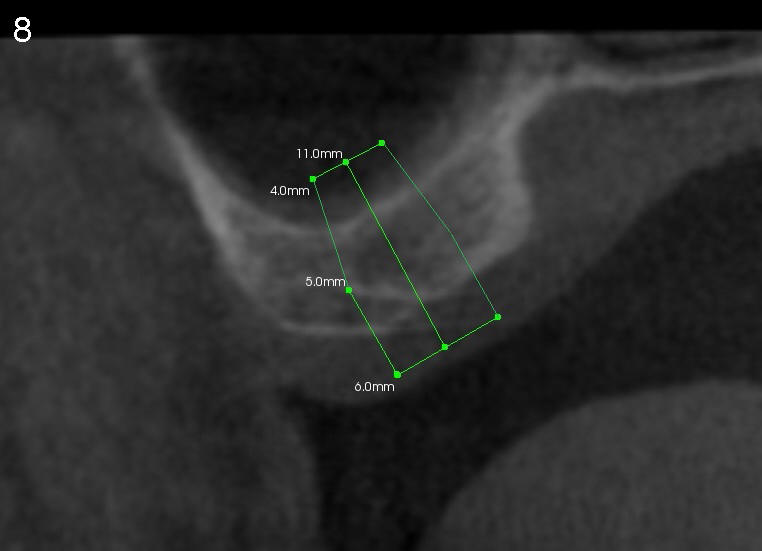

A trephine bur with outside diameter 4 mm will be used to create osteotomy and harvest the bone core (Fig.3; white lines). If the bone does not come out with the trephine bur, it will be pushed upward slowly and gently with a flat end osteotome or tap (Fig.4). When an implant is placed (Fig.5 red outline; 6x11 mm), it is covered by the vital bone above with blood supply coming from the sinus membrane.

Fig.7,8 are CT coronal sections, showing #2 ridge morphology and implant design, respectively.